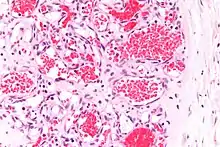

![]() | Aspiration pneumonia | Lung tissue where alveoli contain hemosiderin-laden macrophages and occasional multinucleate giant cells as well as red blood cells. | Category: Histopathology of aspiration pneumonia | Aspiration pneumonia |